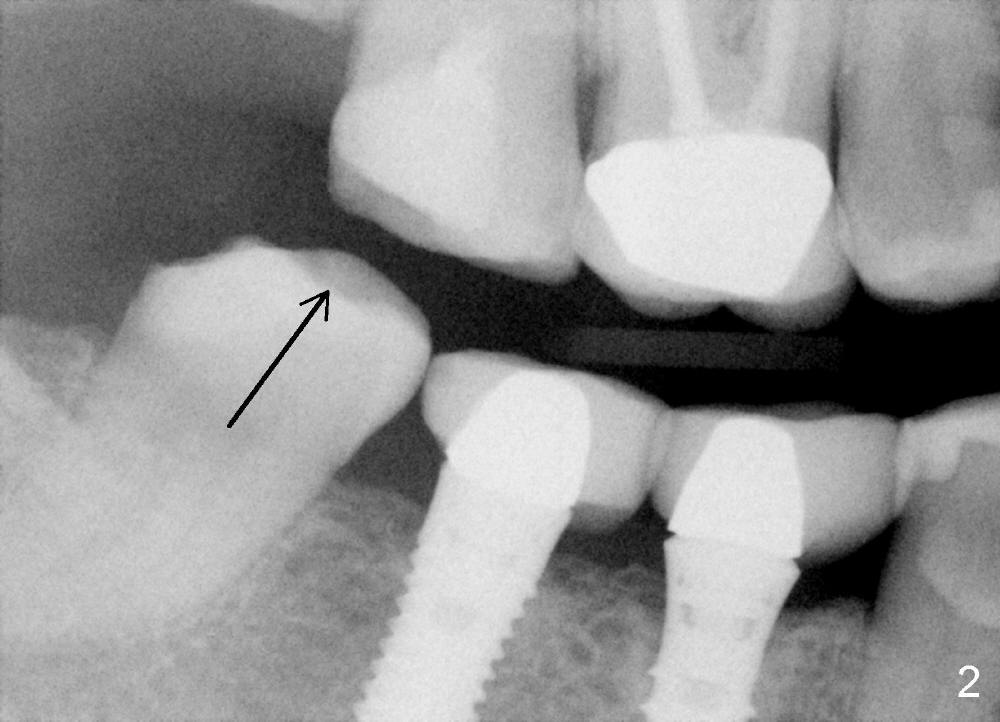

A 51-year-old lady has multiple restorations (Fig.1-3), e.g., amalgam (A in Fig.1) of the upper right 2nd molar as well as history of pulpotomy. The 1st molar has periapical radiolucency (* in Fig.1) and needs root canal therapy. The lower 3rd molar occludes (Fig.2 arrow) with the upper 2nd molar. The latter fractures subgingivally (Fig.3 <) and is extracted with a large MB root (Fig.4) and MB socket (Fig.5). The gingival one third of the palatal wall is defective, as indirectly indicated by granulation tissue palatally (Fig.5 <). So the osteotomy for the immediate implant will not be placed in the palatal socket. The septum is pointed coronally. The pointed portion of the septum is removed; initial osteotomy is formed by 1.5 mm pilot drill in the septum, followed by 2-5 mm osteotomes with the depth of 17 mm. The enlarging osteotomy is deviating buccally; drills are being used to move the osteoomy palatally without much success. When a 5 mm tap is inserted, it is stable and appears to be inside the maxillary sinus (Fig.6). In fact the osteotomy has bony walls around (Fig.7 <), including apical, when the tap is removed. Preop PA shows that the palatal root is apical to the sinus floor (Fig.1 between arrows).